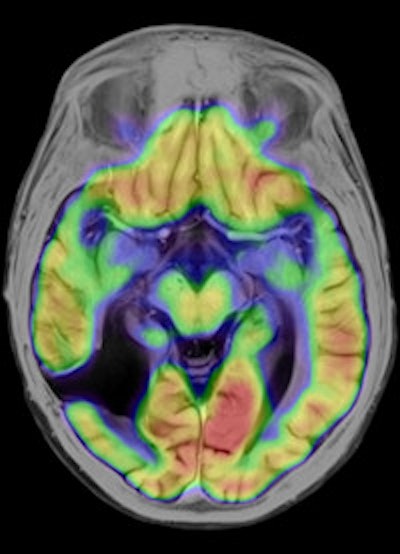

Dr. Alexander Drzezga, from the university's department of nuclear medicine, has been responsible for setting up the system, which was delivered in November 2010. It is currently being used to scan up to five patients a day, but that number is likely to grow as the Munich team explores the limits of the unit's clinical potential. "Many neurological conditions are suitable for evaluation with PET/MR, including neurodegenerative disorders, dementia, epilepsy, and brain tumors. With regard to evaluation of the cardiac system, combined imaging of PET and MR may also show diagnostic advantages, while inflammation and vascular conditions are also areas of interest," he explained.

Drzezga believes that combining the two modalities offers a number of clinical advantages, not least in eliminating the need for separate diagnostic examinations. Furthermore, the exact anatomical registration of structural and functional/molecular information may improve allocation of suspect findings and improve image quality, for example by motion correction of regions of the body that do not remain rigid during examination. The Munich team will also be exploring how the performance of PET/MR compares with that of PET/CT. There is some evidence that the superior soft-tissue contrast achievable with the newer system will offer significant benefits, even before physicians consider the safety issues involved with any radiation-based imaging technology such as PET/CT, Drzezga suggested.